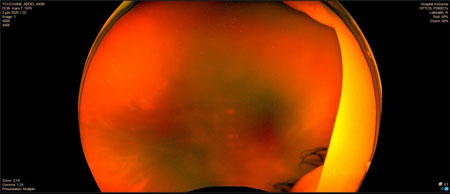

DR tractionnel préop

DR tractionnel post op